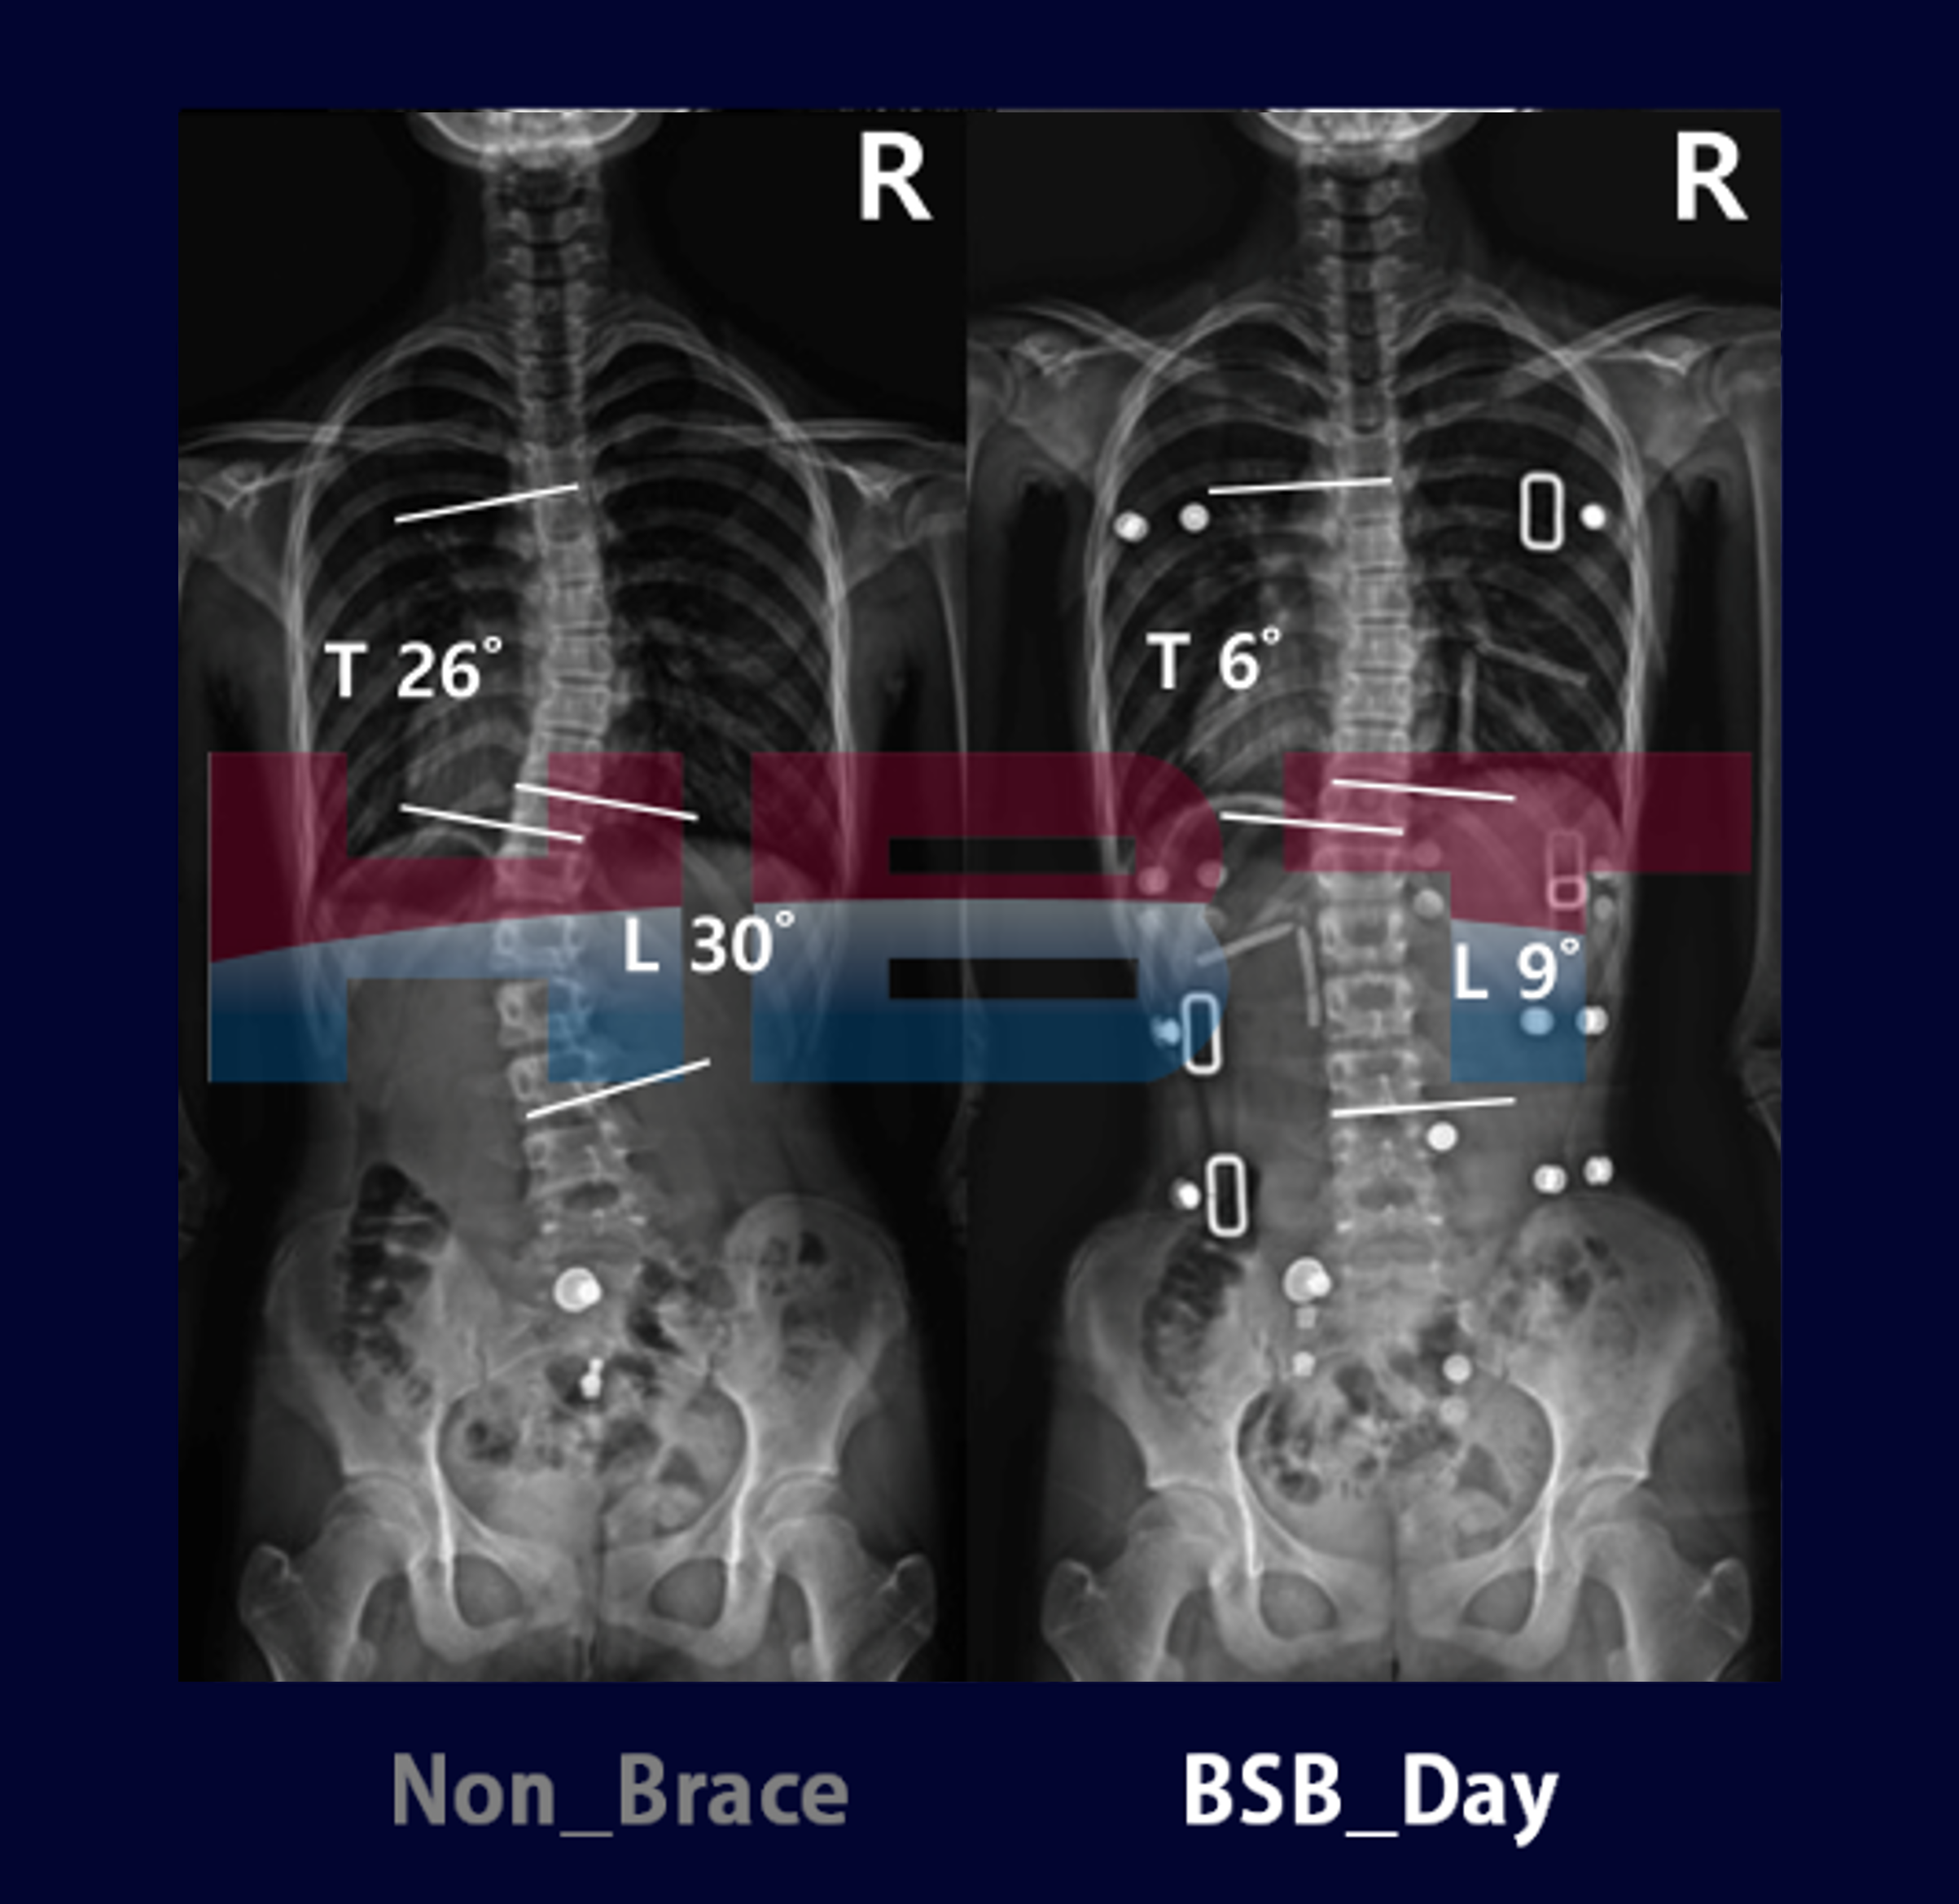

척추측만증 사례_15

척추측만증 사례_14

척추측만증 사례_13

척추측만증 사례_12

척추측만증 사례_11

척추측만증 사례_10